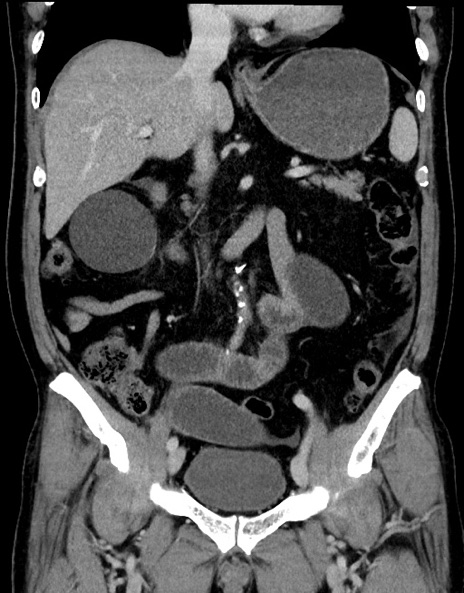

横断像

【症例】70歳代男性

【主訴】腹痛

【現病歴】今朝から腹痛あり。全体的に痛い。特に左上の方。排ガスが今日はない。冷や汗が出る。

【既往歴】直腸癌術後

【身体所見】左側腹部〜上腹部に圧痛あり。腹膜刺激症状明らかなではない。軽度反跳痛。左下腹部に術後瘢痕あり。

【データ】WBC 7700、CRP 0.02